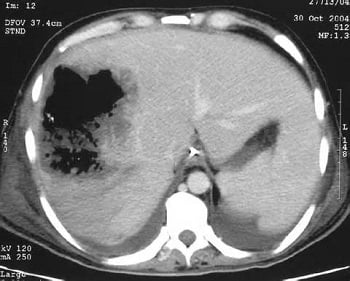

- Компьютерная томография или УЗИ позволяют визуализировать пространство с гнойной жидкостью в печени вместе с сопутствующим отеком. Опытный специалист должен отличить абсцесс печени от возможных опухолей или кист.